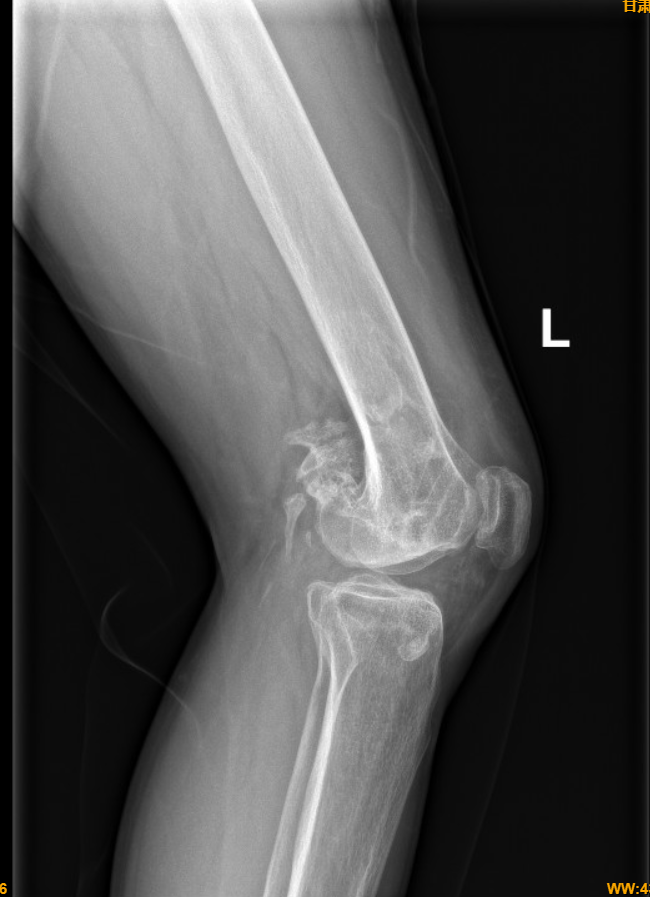

2年前,小林(化名)外伤致左侧股骨内侧髁撕脱骨折合并严重异位骨化,多方求医,多次手术,治疗效果不佳,不能正常行走、下蹲,严重影响日常生活。经亲友推荐,小林慕名找到成人导航 骨科张海军主任,张主任详细询问病情、认真查体,确诊为膝关节创伤性关节炎,伴有股骨内侧髁缺损、内侧副韧带缺如、膝关节严重不稳。确诊后,张主任带领团队与科室迅速展开讨论,并请国内专家会诊,给予了精准治疗方案“旋转铰链膝关节置换术”。

在确定治疗方案后,张主任团队立即实施手术,为患者进行旋转铰链膝关节置换术,该手术技术含量高、难度大,对医师的技术水平和临床经验有更高的要求,为成人导航 首例。